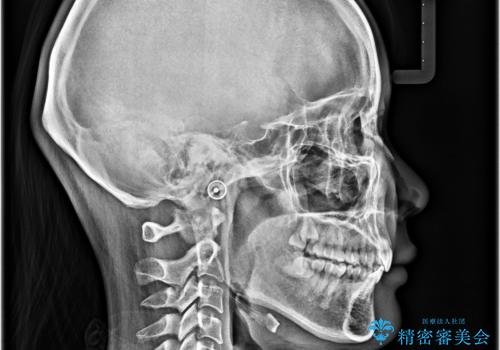

上下歯列の前後位置を見ると、上顎が全体的に前方に位置しており、上顎前歯が前方に突出しているものの、横顔の印象はそれほど口元が突出しているものではない状態でした。

口元を極端に引っ込めた印象にしないため、上顎は左右第一小臼歯2本を、下顎は左右第二小臼歯2本を抜歯し、ワイヤー装置にて矯正治療を行うこととしました。

上下の抜歯位置を変えることで、左右ともに理想的な咬み合わせを達成することができました。

横顔の印象はほとんど変わらないものの、唇を閉じたときに前に出ていた下唇が、治療後には少し下がった状態に仕上げることができました。